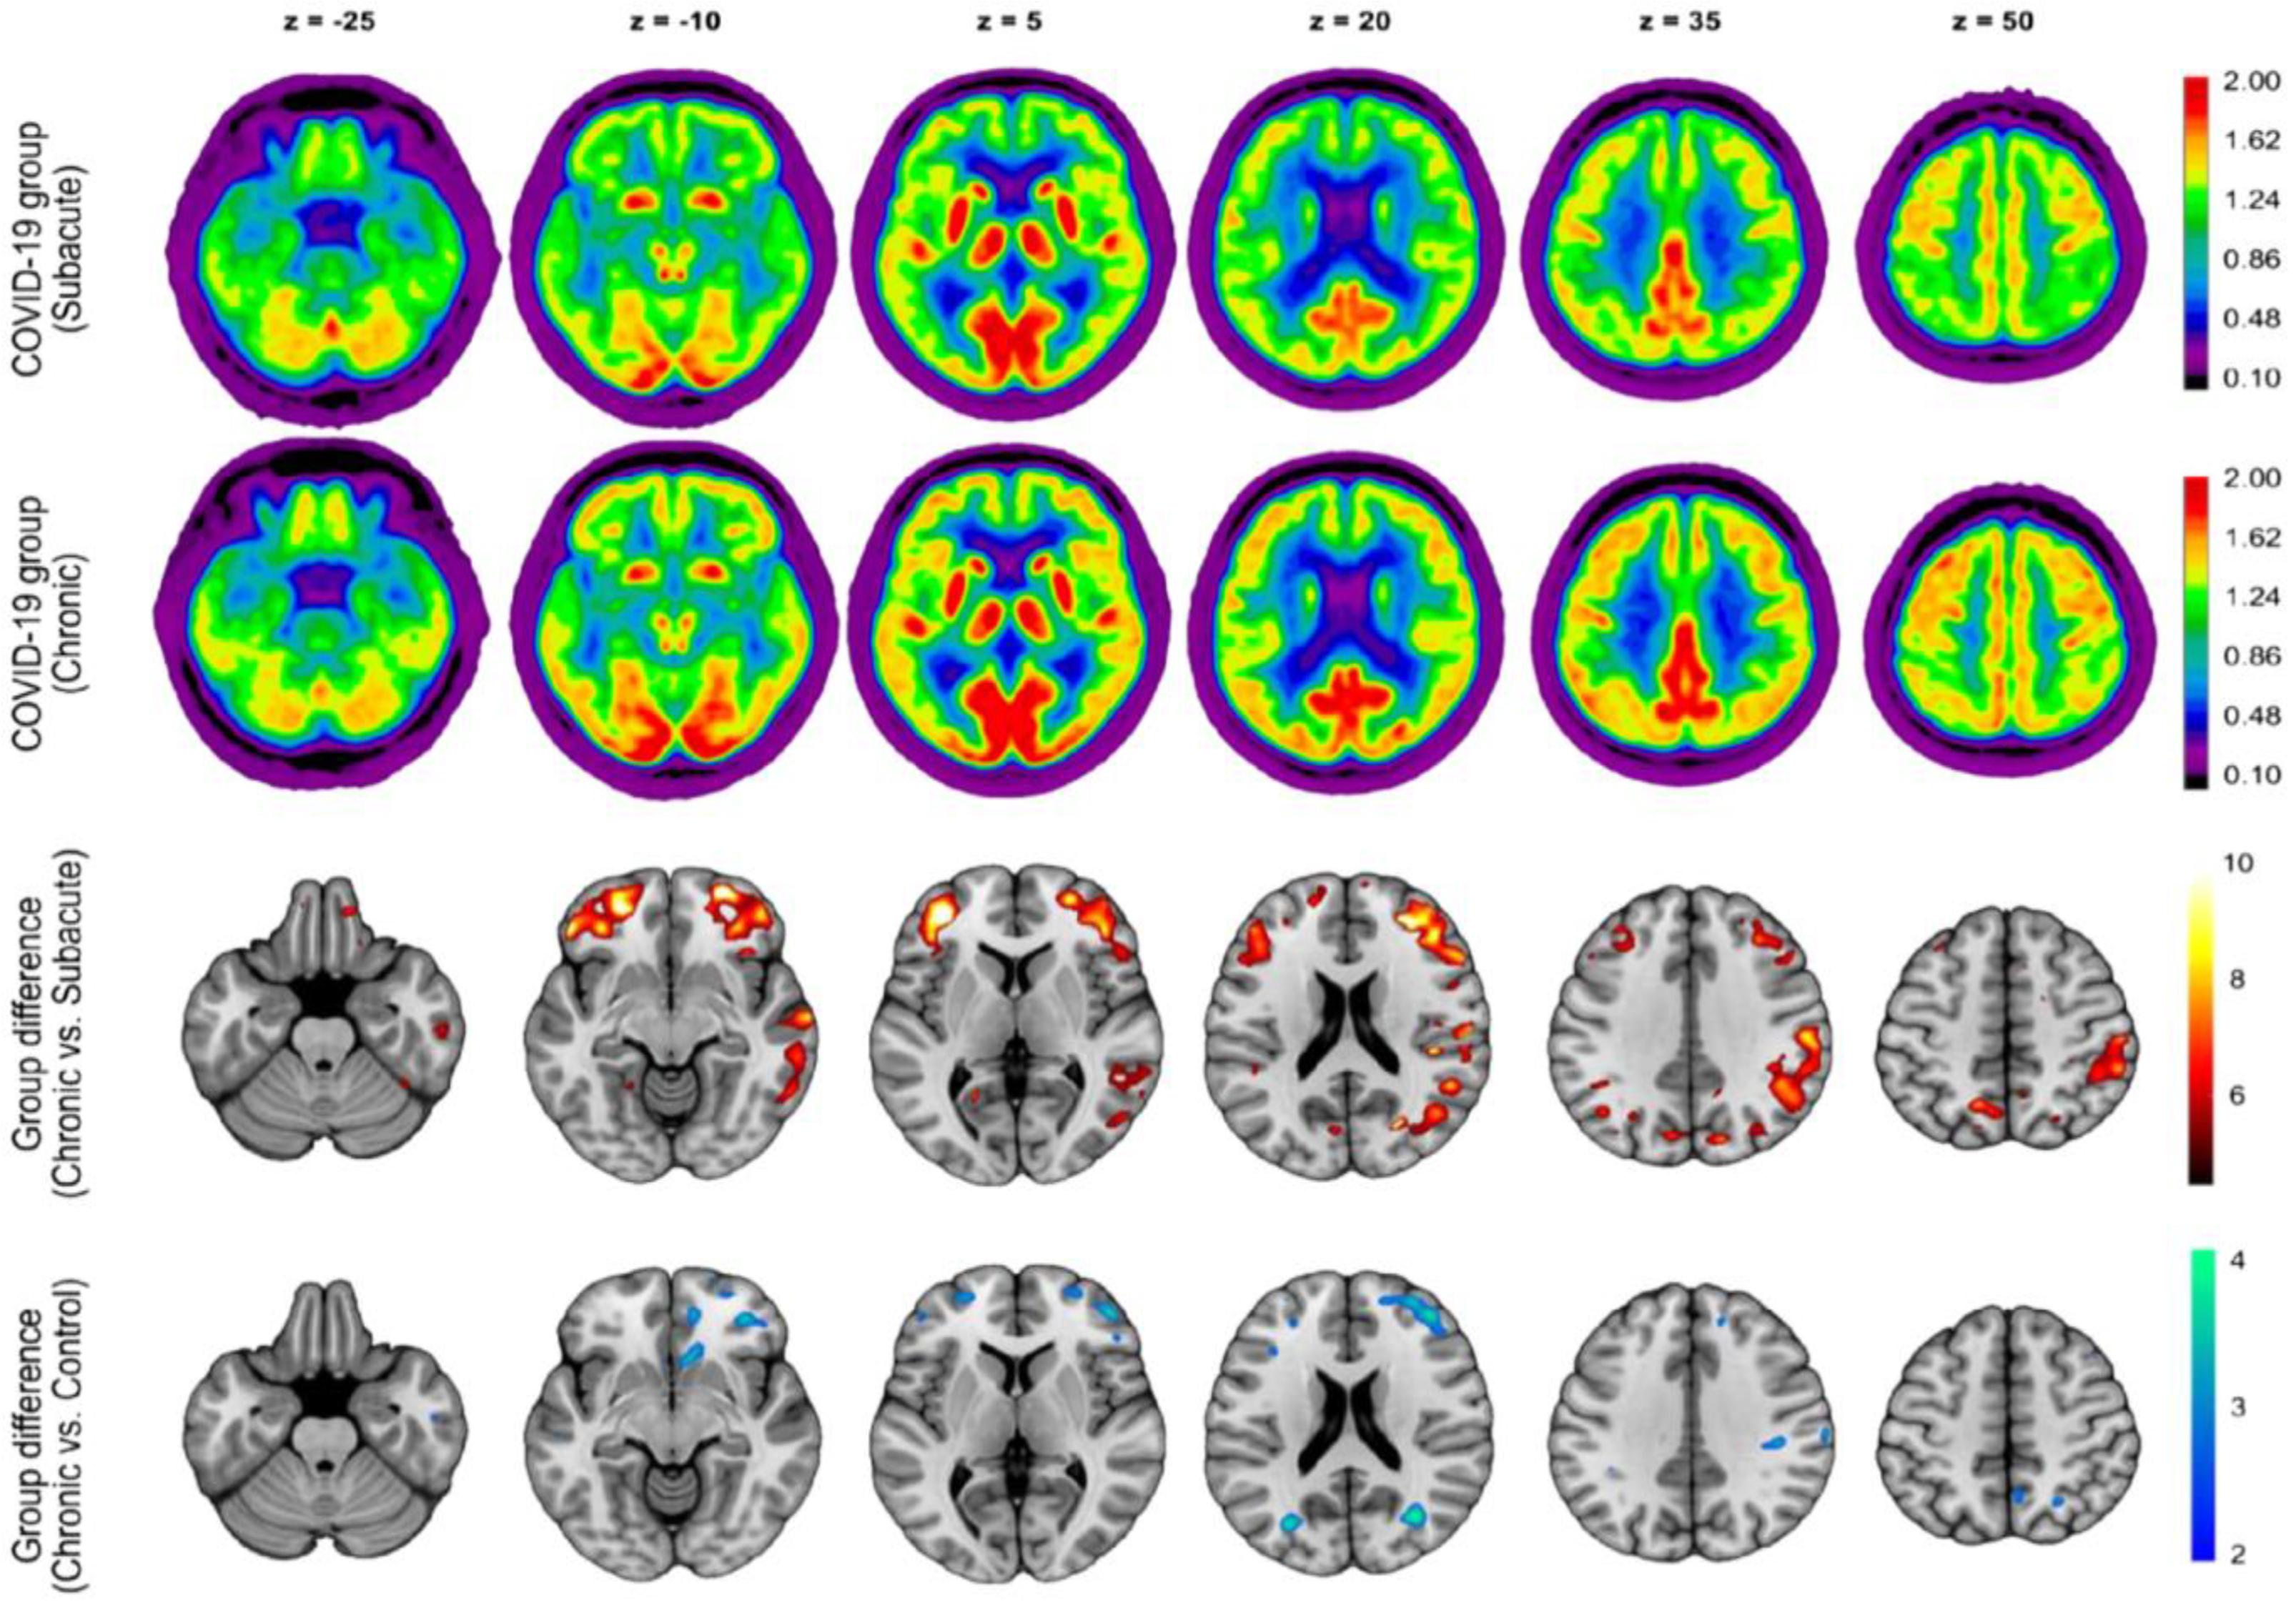

- Blazhenets, G.; Schröter, N.; Bormann, T.; Thurow, J.; Wagner, D.; Frings, L.; Weiller, C.; Meyer, P.T.; Dressing, A.; Hosp, J.A. Slow but Evident Recovery from Neocortical Dysfunction and Cognitive Impairment in a Series of Chronic COVID-19 Patients. J. Nucl. Med. 2021, 62, 910–915. [Google Scholar] [CrossRef] [PubMed]

- Dressing, A.; Bormann, T.; Blazhenets, G.; Schroeter, N.; Walter, L.I.; Thurow, J.; August, D.; Hilger, H.; Stete, K.; Gerstacker, K.; et al. Neuropsychologic Profiles and Cerebral Glucose Metabolism in Neurocognitive Long COVID Syndrome. J. Nucl. Med. 2022, 63, 1058–1063. [Google Scholar] [CrossRef]

| Blazhenets et al. [55] | Frontoparietal and temporal regions | Mild cognitive impairment (assessed using MoCA) | 6 months (approximately) | Prospective cohort/8 subjects (6 males and 2 females) |